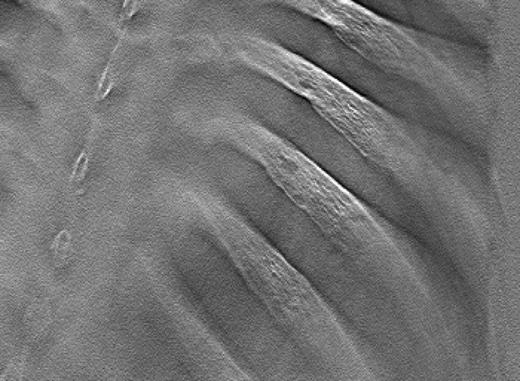

Sample lytic lesions on DT: